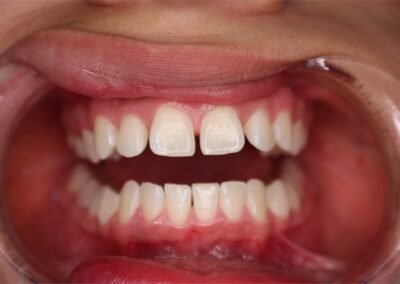

Many of us are not born with picture perfect teeth. For the straight teeth and alignment many people are searching for, braces is a common and effective treatment. Precision Dental Care uses the latest X-Ray technology to trace and model your teeth for your unique dental needs. From crooked teeth to alignment issues, braces can solve a variety of oral concerns.

Before and After Gallery